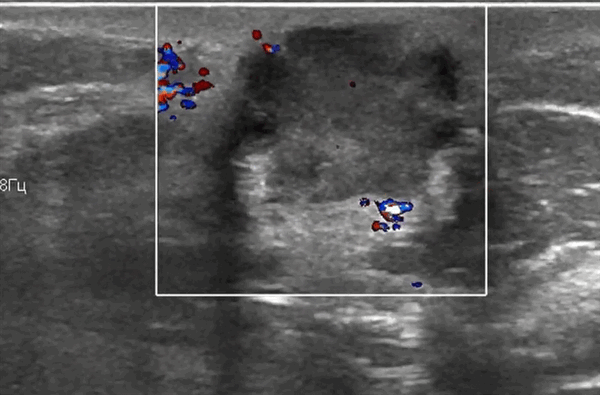

На УЗИ молочных желез в Красноярске мы часто сталкиваемся с распространенным злокачественным образованием, которым является рак. Это то заболевание, с которым дифференцируют все доброкачественные изменения в молочной железе. При опасении на наличие злокачественного образования на УЗИ молочных желез необходимо оценить его контуры, эхоструктуру, место расположения, количество, размеры и форму, дополнительные акустические эффекты, затем оценить состояние протоков и окружающих тканей, в том числе кожные изменения, а также наличие и выраженность васкуляризации. По нашим данным, наиболее типичными знаками для злокачественности опухолевого образования грудной железы являются: неровные контуры с нечеткими границами более чем в 60%, формы распределены равномерно на одну треть случаев (амебообразная, округлая или неправильная). Ориентация образования на УЗИ чаще бывает неопределенная (60%), чем вертикальная (30%) или горизонтальная (10%). Внутренняя эхоструктура в двух третьих случаев гипоэхогенная однородная и в одной третьи случаев неоднородная. Локальная компрессия в 80% случаев не изменяет форму образования, а в половине случаев изменяется состояние кожи над очагами. Можно также в 75% ультразвуковых исследований определить сосудистый рисунок с беспорядочным распределением цветных сосудистых сигналов внутри опухоли.

При диффузной форме рака цветное и энергетическое допплеровское картирование выявляют сосудистые сигналы, расположенные хаотично во всех квадрантах пораженной грудной железы на фоне расширенных лимфатических сосудов.

Узловая форма рака грудной железы на УЗИ может обнаруживаться в виде единичных или множественных узлов. Размеры опухоли обусловлены темпами роста и временем их выявления. Имеется особенность ультразвуковых срезов двух морфологических вариантов узловой формы раков грудной железы — четко отграниченных опухолей с экспансивным характером роста и плохо отграниченных раков (скиррозного или звездчатого) с инфильтративным типом роста. При экспансивном (раздвигающем) типе роста опухоли имеют правильную округлую или овальную форму, хорошо очерченные или немного размытые контуры. Опухоль проникает в окружающие ткани, при этом происходит их сжатие и деформация, но не разрушение.